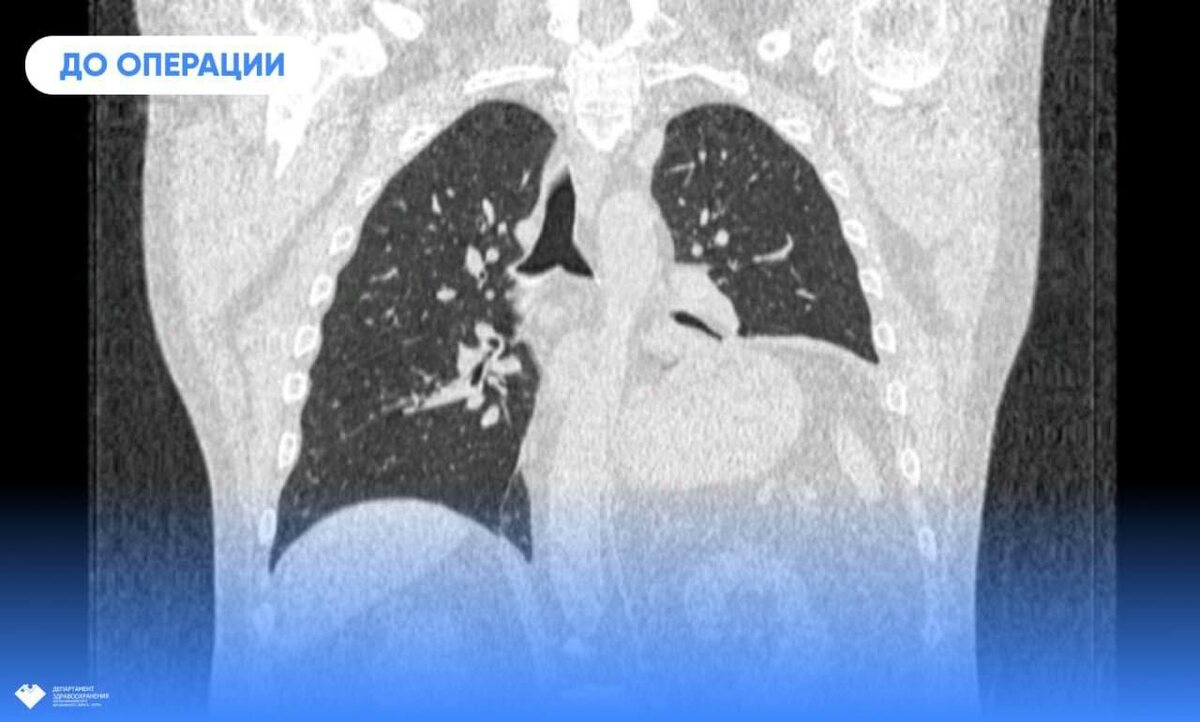

Юрий Шавров задыхался даже при малейших физических нагрузках. Как выяснилось при обследовании, его левое лёгкое сдавила диафрагма, из-за чего доля не могла полноценно выполнять свою функцию. Врачи травмцентра выполнили пластику диафрагмы. «Операция ювелирная, поскольку толщина диафрагмы не превышает 5 миллиметров, и есть риски повредить окружающие структуры», - рассказали в травмцентре. С задачей справились заведующий хирургическим отделением травмбольницы Дмитрий Горлов и врач-хирург Евгений Николаев. Они выбрали малоинвазивную методику, избежав травматического полостного доступа. Сразу после операции Юрий Александрович почувствовал улучшение самочувствия. Одышка больше не беспокоит, и сегодня он вновь может дышать полной грудью.

Юрий Шавров задыхался даже при малейших физических нагрузках. Как выяснилось при обследовании, его левое лёгкое сдавила диафрагма, из-за чего доля не могла полноценно выполнять свою функцию. Врачи травмцентра выполнили пластику диафрагмы.